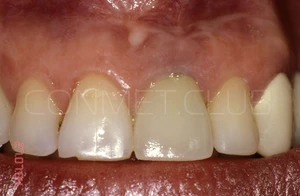

Ситуация в полости рта через 10 лет после операции. Обратите внимание на сохранность межзубных сосочков около имплантата и полное отсутствие рецессии десны на поддесневой, полированной части имплантата.

Фото этой же коронки через 15 лет после операции.